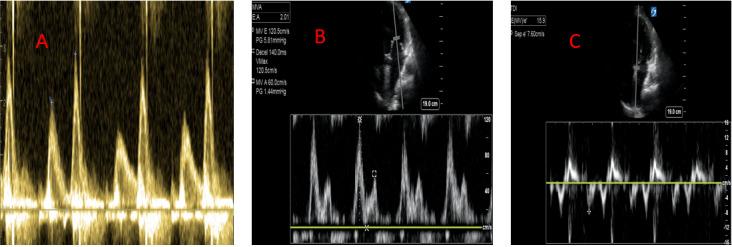

急性肾损伤(AKI)对于入住重症监护病房(ICU)的患者而言是一个重大问题,这是由于其发病率高且伴有死亡率,需要肾脏替代治疗(RRT)的AKI发生率超过5%,而AKI的死亡率超过60%[1,2]。超声可用于识别有AKI风险的患者并辅助进行AKI管理。ICU中AKI的危险因素不仅包括低灌注,还包括静脉淤血和容量超负荷。容量超负荷和血管淤血与多器官功能障碍及更差的肾脏预后相关。每日及总体液体平衡、每日体重以及水肿的体格检查可能不准确,且会掩盖真正的全身静脉压[3,4,5]。床旁超声可让医护人员评估血管血流模式,并对容量状态进行更可靠的评估,以指导并个体化治疗。超声检查的心脏、肺部和血管模式可识别前负荷反应性,应评估前负荷反应性以安全地管理正在进行的液体复苏,并评估液体不耐受的迹象。在此,我们概述了床旁超声的应用,特别强调以肾脏为中心的策略,即在识别肾损伤类型、评估肾血管血流、静态测量容量状态以及对危重症患者进行容量优化的动态评估方面的应用。